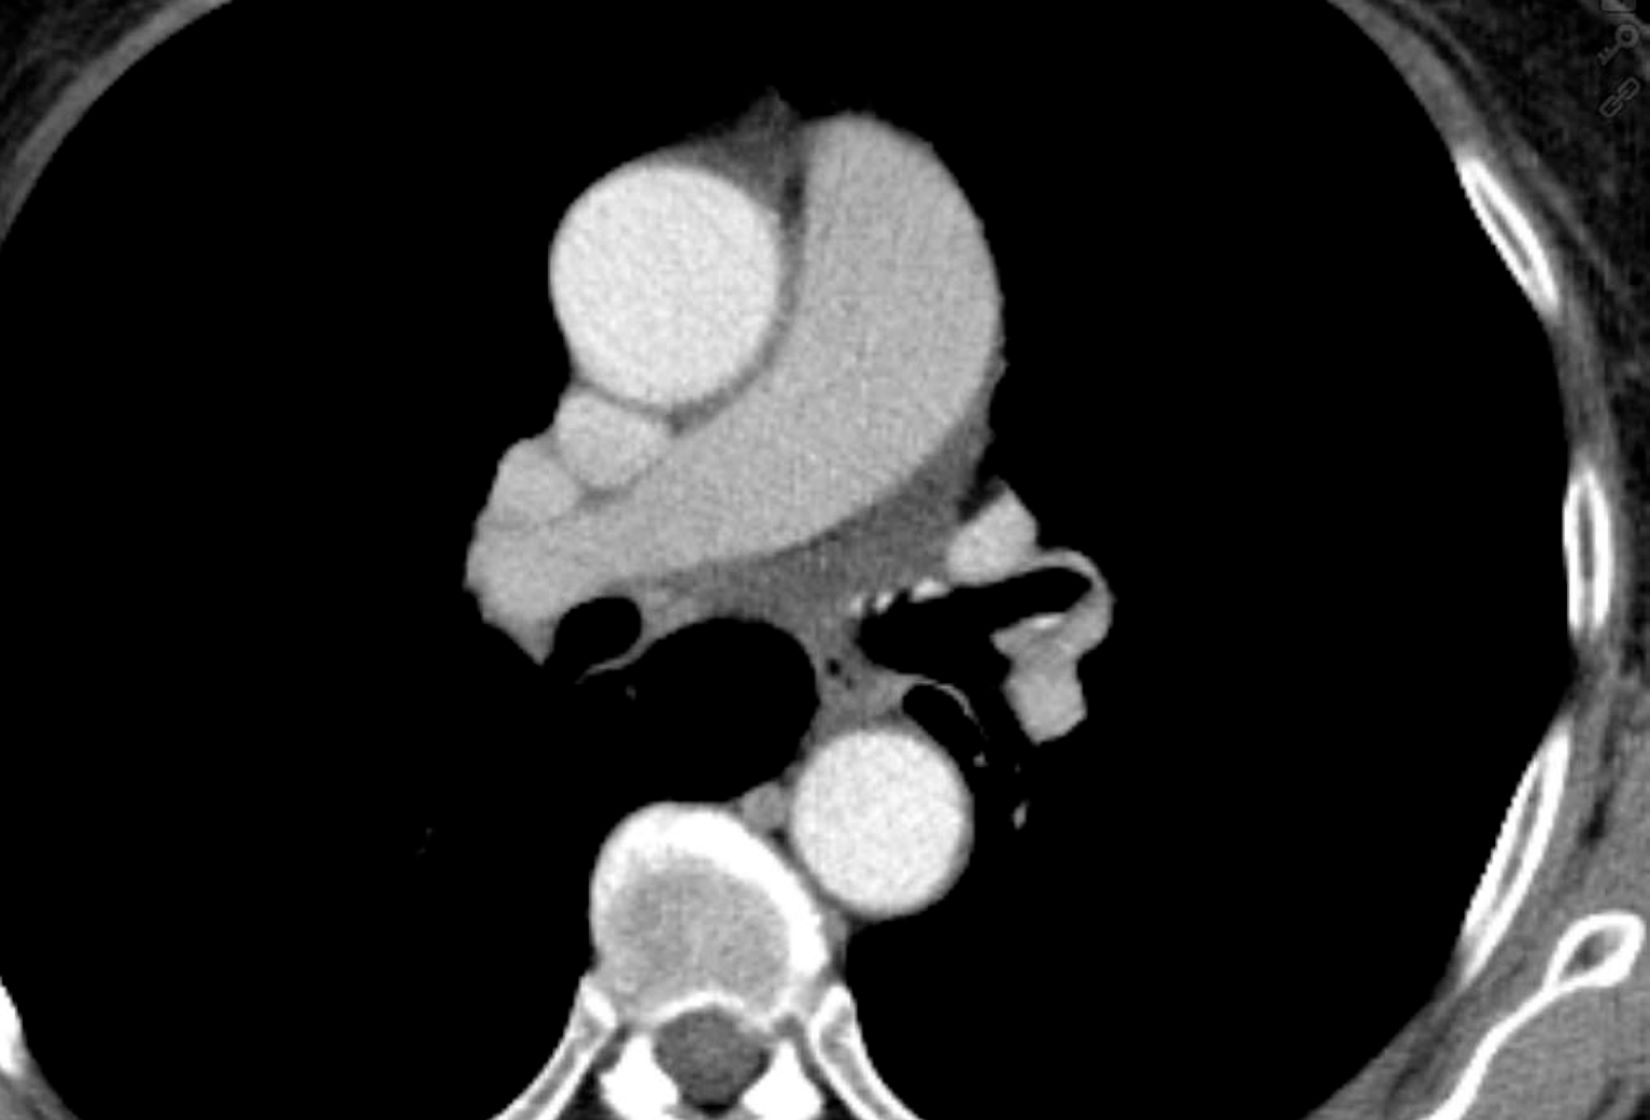

Neben dem Ultraschall und dem konventionellen Röntgen wird vielfach für das weitere therapeutische Vorgehen die Schnittbilddiagnostik eingesetzt. Dazu gehören die Computertomographie (CT) und die Magnetresonanztomographie (MRT). Bei diesen Untersuchungen werden bestimmte Bereiche des Körpers so untersucht, dass auch kleinste Gewebeveränderungen genau dargestellt werden.

An beiden Standorten, der DIAKO und dem Malteser Krankenhaus, können CT-Untersuchungen durchgeführt werden. Des Weiteren gibt es die Möglichkeit in der DIAKO bestimmte Patientengruppen auch mittels sog. Low-Dose-(Niedrig-Dosis-)-CT-Protokollen zu untersuchen.